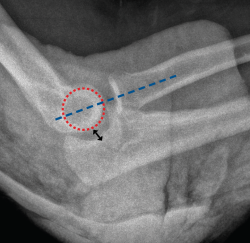

Figura 6. Radiografía lateral de codo tras una maniobra de reducción de una luxación donde puede verse cómo el eje longitudinal del radio se encuentra alineado con la bisectriz del capitellum. Además, puede observarse un drop sign positivo (flecha negra). Este signo corresponde a un aumento de la distancia ulnohumeral de > 3 mm.

Tras la reducción de un codo luxado, en la evaluación radiográfica, el eje longitudinal del radio debe pasar por la bisectriz del capitellum (Figura 6). En ocasiones, puede apreciarse también un drop sign positivo(17)(Figura 6), que corresponde a un aumento de la distancia ulnohumeral de > 3 mm. Son signos de inestabilidad persistente de codo una mal alineación radiocapitelar tras la reducción y un drop sign persistente en las radiografías de control sucesivas.